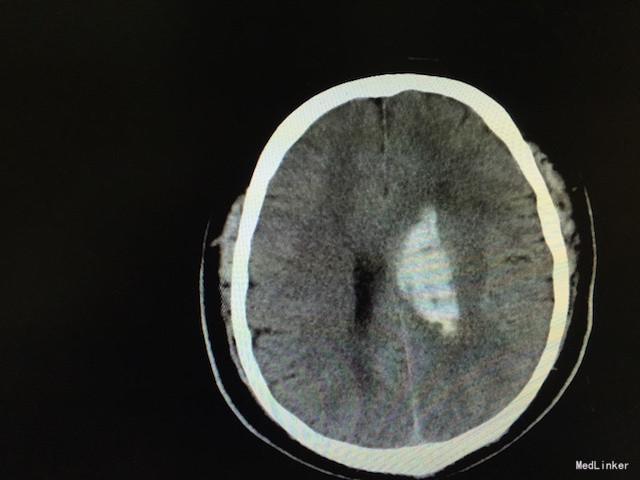

查体:右侧“三偏征”明显(偏瘫、偏身感觉障碍、偏盲),右病理征可疑阳性。 辅助检查:急诊行头颅CT,如下图,左侧基底节区出血。

诊断:脑出血 高血压3级(极高危) 治疗:安静卧床、脱水降颅压、冰帽降低脑组织代谢、调整血压、止血治疗等。